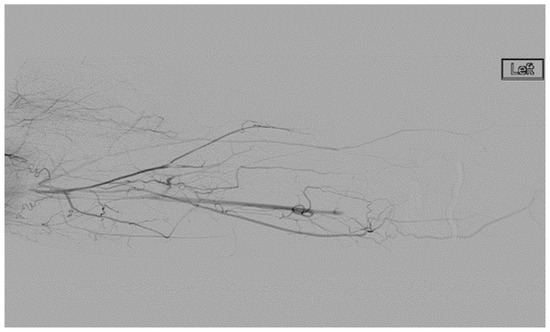

A heparin drip was then initiated, and she was taken to the catheterization lab for thrombolysis. This was carried out with Alteplase for 48 h as the patient had strong collaterals and was not in limb-threat (Figure 7, Figure 8, Figure 9, Figure 10 and Figure 11). However, her radial artery remained occluded. She was then taken to the operating room for thromboembolectomy of the left brachial and radial arteries (Figure 12). She was continued on anticoagulation post-operatively and was discharged.

Figure 7.

Left subclavian arteriography demonstrating a thrombosed brachial artery at the mid-humeral level and extensive collateralization proximally.

Figure 8.

Left subclavian arteriography in an ATOS patient in stress position demonstrating a totally occluded subclavian artery.

Figure 9.

Distal left arm angiography in an ATOS patient demonstrating an occluded radial artery at the origin and ulnar artery at the mid-forearm.

Figure 10.

Angiography of the radial and ulnar arteries as well as the palmar arch and digital branches in an ATOS patient with a brachial thrombus.

Figure 11.

Distal brachial artery thrombosis in an ATOS patient.